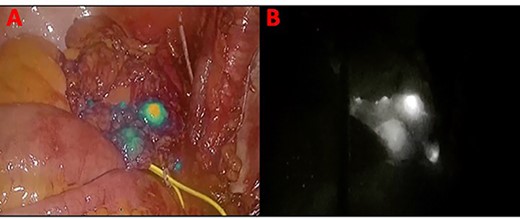

In November 2020, for a diagnosis of prostate cancer at prostatic biopsy, we intraoperatively performed ICG fluorescence-guided lymphography during a laparoscopic radical prostatectomy with pelvic lymphadenectomy. ICG was injected in the prostatic tissue of the patient transrectally through ultrasound identification of the gland. A fine needle was used connected to a 10 cc syringe, taking care to aspirate before injecting the tracer in order to avoid blood vessels. A dedicated laparoscopic high-definition camera system, provided by Karl Storz, was used in our case. This system allowed the surgeon to easily switch from White Light (WL) mode to ICG mode. For this reason, it was very simple to compare WL and ICG mode images. Furthermore, this technique is inexpensive, requiring only a small dose of ICG. Therefore, soon after ICG injection, the lymphatic vessels were identified in the pelvic cavity as fluorescent linear structures running side by side to the iliac vessels. Figure 1 shows the fluorescent lymph nodes in the obturator fossa. Then, using the ‘intensity map’ function (also called ‘overlay function’), lymph nodes can be seen as white structures as this function uses WL (instead of blue light) and eliminates the colors, as shown in Fig. 2. Surgical dissection was therefore performed, avoiding iatrogenic damage to major lymphatic structures. On histological examination, the prostate gland was found to be affected by an acinar adenocarcinoma (with Gleason Score 8, 4 + 4) involving ~20% of the right lobe and 35% of the left lobe. Twenty-four lymph nodes sent as obturators (15 on the right and 9 on the left side) and 10 lymph nodes sent as external iliacs (6 on the right and 4 on the left side) were free from metastases. The patient was discharged 5 days after surgery, and 6 months after surgery, he did not show any complications related to lymph node dissection.

The blue arrow shows the lymph nodes which, due to the effect of indocyanine, take on a fluorescent green color. The yellow arrow indicates the obturator nerve.

Panel (A) shows the lymph nodes in green color when the blue light is used. Panel (B) shows the lymph nodes in white when the ‘overlay’ function is used.